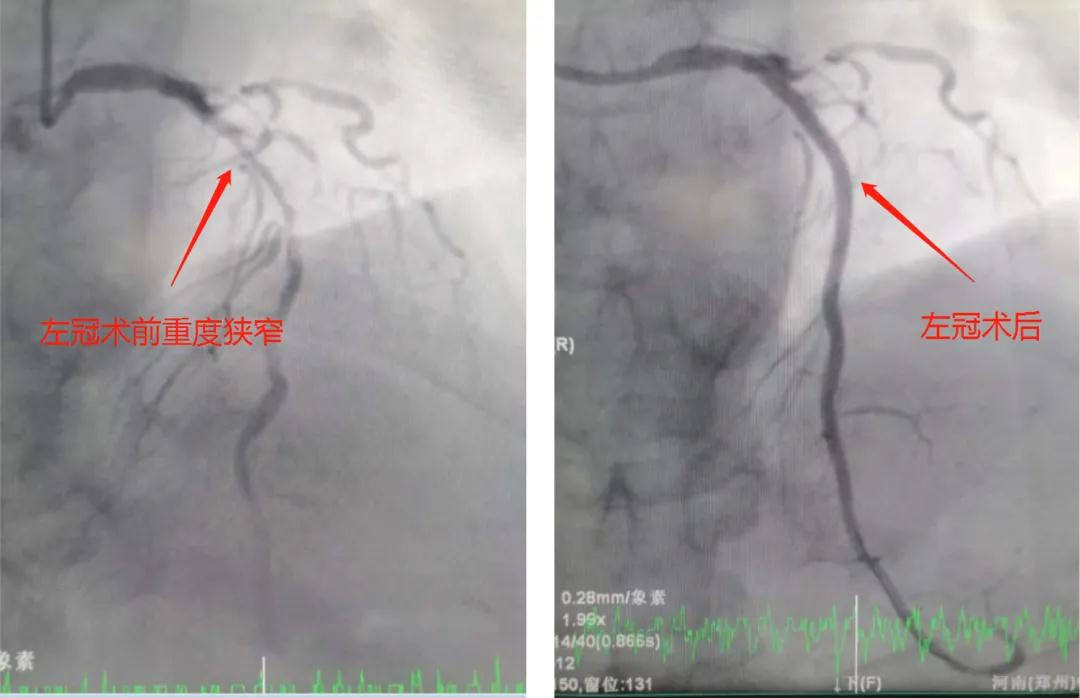

(左图为心脏支架植入前几乎闭塞,右图支架植入后恢复正常)

时间一分一秒过去,一个接一个病人顺利地完成支架植入手术,原来闭塞的、狭窄的血管,在开通地一瞬间,一股血流顺利地通过原本不通畅的血管流向冠脉远端,在那一刹那,病人自觉一下子心胸豁然开朗,无比舒畅,而医务人员的心也随之轻松了许多。

(左图为心脏血管支架植入前完全闭塞,右图支架植入后恢复正常)